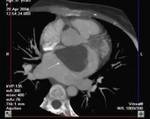

Methods: Twenty-two patients referred to our department with a suspected cardiac mass, previously detected by cardiac ultrasound, were evaluated by CT (12 patients) and MRI (4 patients). Six patients were examined by both modalities. In 2 cases of staging of a known primary neoplasm and one case of a suspected epicardiac lesion, positron emission tomography (PET-CT) was performed. The CT cardiac examinations were performed using a 16-slice multislice scanner with ECG gating. The MRI examination was performed on a 1.5 Tesla MRI scanner using an ECG-gated cardiac protocol and the PET-CT examination was performed on an integrated PET-CT four-slice scanner, using 370 mMBq of fluorodeoxyglucose.

Results: Twenty-two cardiac masses were successfully detected and their characteristics adequately delineated, including eight myxomas, one angiosarcoma, one ventricular lymphoma, one endocardiac metastasis, one epicardiac paraganglioma, and 10 cases of intracardiac thrombi.